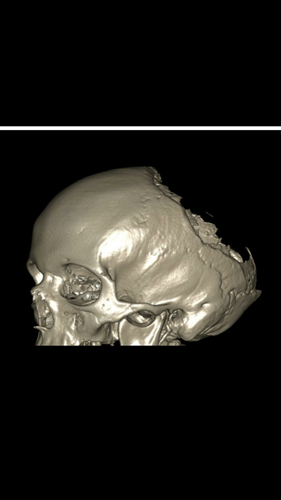

Above is pictures of Sarah's skull were Gorhams is present. Its also known as a bone vanishing disease which is quite clear on that picture.